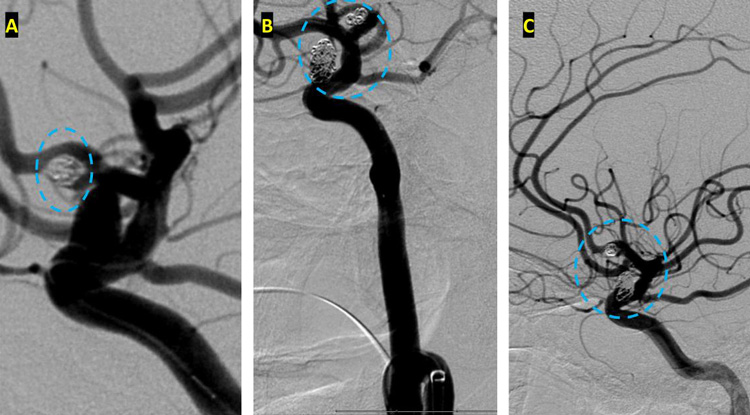

On admission, she presented as a GCS 3, was intubated, and stabilized hemodynamically in preparation for emergent catheter cerebral angiography, which revealed 2 discrete geographically located aneurysms – 1) Anterior Communicating and 2) Right ICA Supra-Clinoid Segment. (Figure 2.)

After careful measurements of the parent vessels, aneurysm sac, and aneurysm neck, we decided to proceed with Primary Coil Embolization of the Acom Aneurysm first, followed by the Right ICA Aneurysm next. Despite greater suspicion in the Acom region, a significant level of uncertainty remained, and we felt it was better to secure both aneurysms if capable of being performed safely. (Figure 4.)